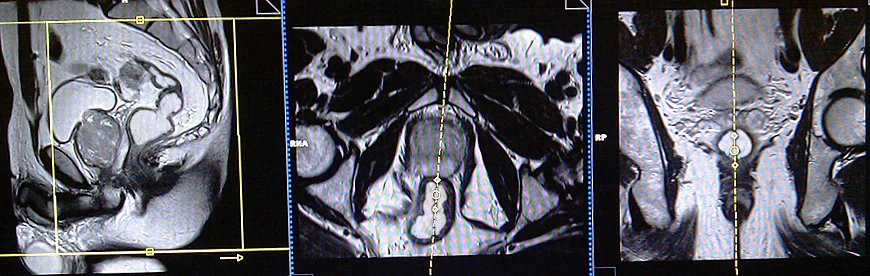

MRI Defecography localiser

A three-plane localizer must be taken at the beginning to localize and plan the sequences. Localizers are normally less than 25 seconds and are T1\T2-weighted low-resolution scans.

T2 tse sagittal 3mm SFOV pre proctogram

Plan the sagittal slices on the axial plane; angle the positioning block parallel to the interpubic fibrocartilage and the anal canal. Check the positioning block in the other two planes. An appropriate angle must be given in the coronal plane (parallel to the rectum and the anal canal). Slices must be sufficient to cover the whole pelvis from the right acetabulum to the left acetabulum. FOV must be big enough to cover the whole pelvis (normally 270mm-300mm). Adding saturation bands on top and front of the sagittal block will reduce artifacts from arterial pulsation and breathing.

T2 tse axial oblique 3mm SFOV pre proctogram

Plan the axial oblique slices on the sagittal plane; angle the positioning block perpendicular to the anal canal. Check the positioning block in the other two planes. An appropriate angle must be given in the coronal plane (perpendicular to the anal canal). Slices must be sufficient to cover the entire anal canal.

T2 tse coronal oblique 3mm SFOV pre proctogram

Plan the coronal oblique slices on the sagittal plane; angle the positioning block parallel to the anal canal. Check the positioning block in the other two planes. An appropriate angle must be given in the axial plane (horizontally across the anal canal or parallel to the right and left hip joint). Slices must be sufficient to cover the whole anal canal.

localiser

T2 TRUFISP cine, small FOV 10mm, 1 second, 150 measurements.

Plan the sagittal slices on the axial plane; angle the positioning block parallel to the interpubic fibrocartilage and the anal canal. Check the positioning block in the other two planes. An appropriate angle must be given in the coronal plane (parallel to the rectum and the anal canal). Slice must be positioned over the middle of the rectum and anal canal.